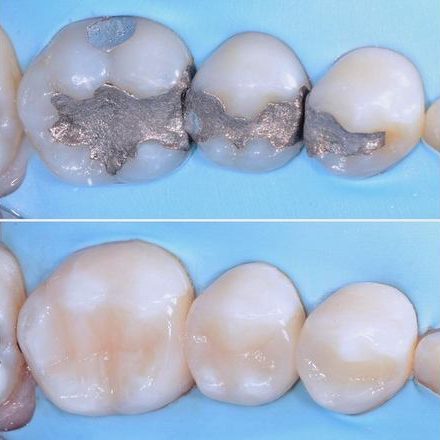

ApprofondisciCONSERVATIVA

La Terapia Conservativa si occupa della sostituzione di parti di dente di dimensioni contenute, compromesse da carie o fratture. Vengono utilizzati materiali particolarmente sofisticati che consentono la fabbricazione del restauro direttamente nel cavo orale.